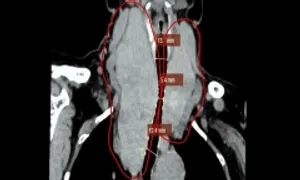

Bướu giáp đẩy lệch khí quản sang trái

24/01/2025

Xem chi tiết